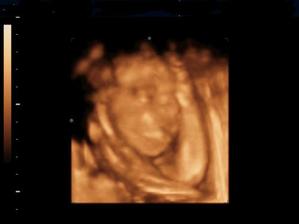

Naše kinderka

Dňa 24.8.2009 o 9.15 sa nám sekciou narodili naše krásne dvojičky Vanesska 2280 g a Larinka 2990 g. Robia nám veľkú radosť a moc ich ľúbime...